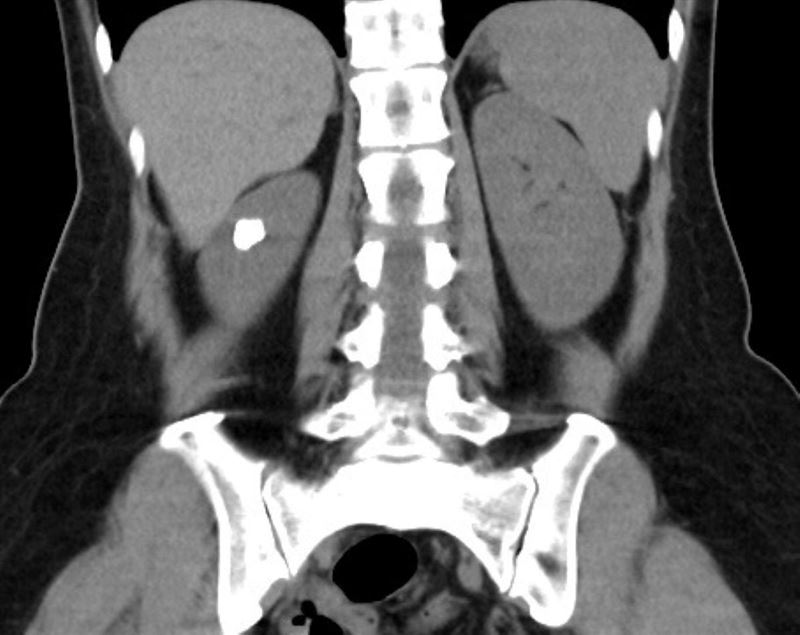

台北慈濟醫院泌尿科醫師鐘伯恩指出,經電腦斷層掃描發現,田女士的左側腎臟內有大約1.5公分的結石群,死死嵌在「腎盞憩室」中。這是一種較為罕見的先天性腎臟結構異常,發生率僅約0.2%至0.6%,腎盞向外擴張形成囊袋狀空間,而憩室與正常腎盞之間的通道竟然「不到1毫米」,導致尿液排空能力極差,久而久之尿液滯留就積成了結石。